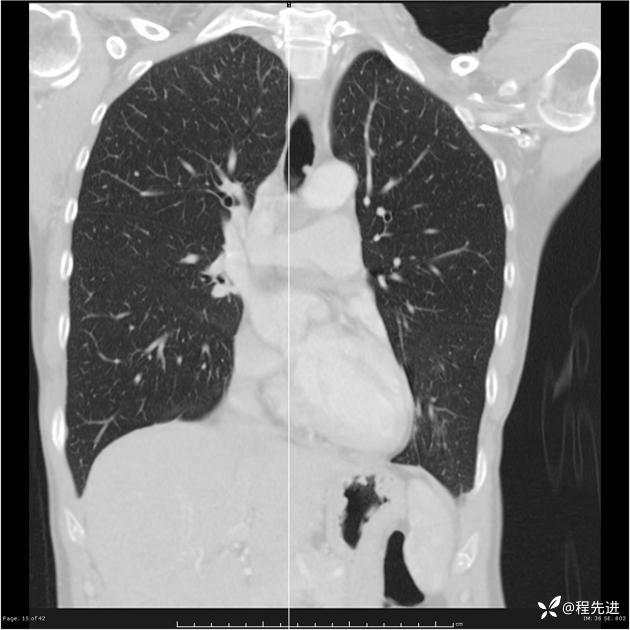

病例女,53岁,气管、左主支气管、下叶支气管内结节,乳头状瘤?期待你的精彩解读

女,53岁

乳头状瘤?